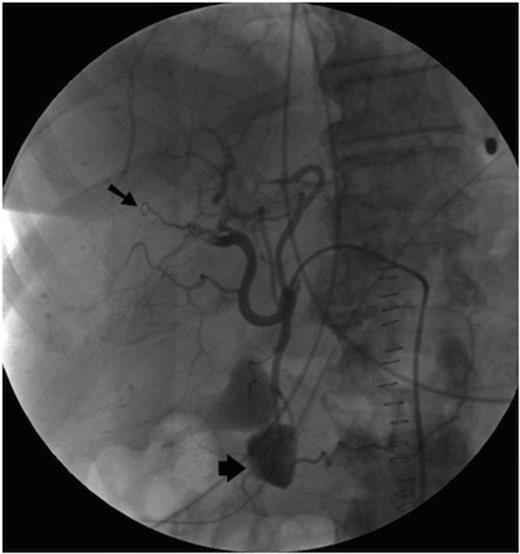

Initially, selective embolisation of the anterior right hepatic artery was performed using small coils (COOK UK) and small particles of grated gelatin sponge soaked in 0.5ml of 5% Ethanolamine. However this proved to be ineffective (Figure 2), and so the posterior branch of the right hepatic artery was embolised, successfully controlling the haemobilia. The left hepatic artery was spared.

Following the procedure there were signs of recurrent haemorrhage such as fluctuating serum haemoglobin levels and some ongoing malaena. However, these ceased spontaneously after a few days, and the patient subsequently made an uneventful recovery.